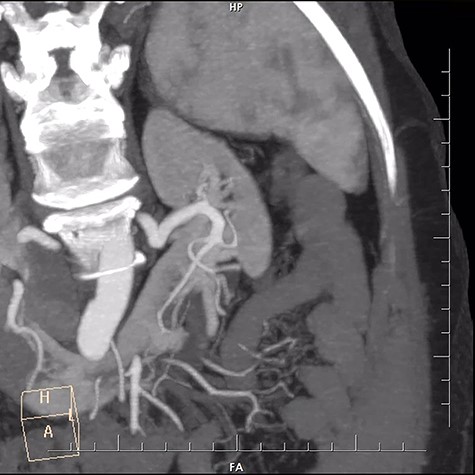

A 29-year-old female patient with end stage renal failure was our recipient. She was considered for a pre-emptive transplant and the only viable living donor was her 59-year-old mother. Upon evaluation for the donor, all the criteria were met except for the detected horseshoe kidney by CT scan. Dynamic CT revealed one renal artery and one renal vein for each side, a long but thin isthmus connecting lower poles with no visible arterial supply (Fig. 1). Sizes of the left and right kidneys were 110 × 38 cm and 117 × 42 cm, respectively. Absence of a connecting caliceal system was established with a descending urography. We did not perform a dynamic renal perfusion scintigraphy to assess the split functions of the kidneys since their sizes, respective vasculature and measured GFR values indicated sufficient capacity for each kidney. Left portion of the kidney was considered for nephrectomy.